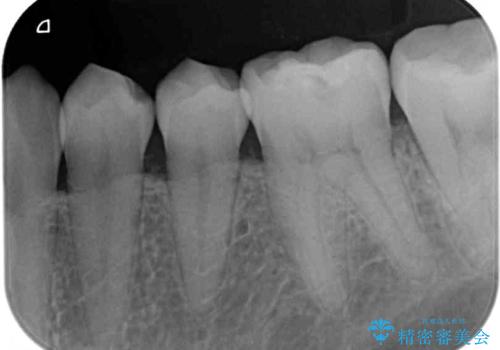

- 左右下顎の奥歯に違和感を感じるとのことで来院された患者様です。

最近ものが挟まりやすくなったり、冷たいものがしみるようになったりと言った症状があり、診査したところ、歯質の欠損や不適修復物などが認められました。

精度の高いセラミックインレーによる修復治療が第一選択となりますが、一方の歯は元々修復物が大きく、咬合力の強い方であったので、セラミッククラウンによる補綴治療を行うこととしました。